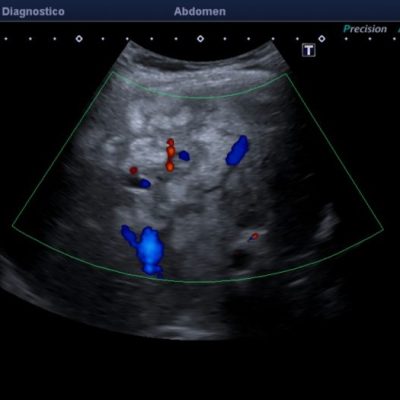

El médico de referencia le indica nueva ecografía de control, donde se observan múltiples y extensas lesiones focales hepáticas hiperecogénicas, redondeadas y confluentes, las cuales predominan en adyacencia a venas supra hepáticas, sin condicionar efecto de masa y sin alteración de la superficie hepática(fig. 1 y 2). Ante la valoración con Doppler color no presenta patrón de flujo peri ni intralesional y respeta el calibre de las venas supra hepáticas(fig. 3 y 4). Dada las características ecográficas se sospecha esteatosis focal multinodular confluente como principal diagnóstico presuntivo, siendo los diagnósticos diferenciales patologías de naturaleza infecciosa, tumoral o metastásica.